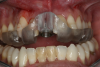

The next case follows the digital protocol for fully guided surgery and prosthetics. A CBCT radiograph, digital impression, and digital photography were the cornerstones to the success of this case. The 3D data set was electronically delivered to the dental laboratory. The data were merged and the process to develop the plan was initiated. The use of CBCT was essential in this case, particularly due to minimal space for placement of individual implants and single-unit crowns. The patient's chief concern was that she wanted to have single-unit crowns instead of fixed crown-and-bridge restorations because she was worried that she would someday find herself in an assisted-living facility; if that were to happen, she wondered, who would help floss under her bridge work? Her decision was to have single implants with individual crowns. CBCT technology is much more accurate in evaluating space maintenance and management.10 Periapicals in the past were rather close for calculating spacing; however, the CBCT identifies the buccal-lingual dimensions as well as the mesial-distal measurements. On review of the completed proposals for implant placement and provisionals, it was determined that there was sufficient spacing for implant placement to allow appropriate emergence profiles for the provisionals and then eventually the final single-unit cemented crowns. The proposal was accepted, and a 3D-printed surgical stent was fabricated, along with the PMMA provisionals (Figure 29 through Figure 35).

Fig 44. Splinted PMMA seated.

Figure 44

Fig 45. Occlusal view of seated PMMA provisionals.

Figure 45